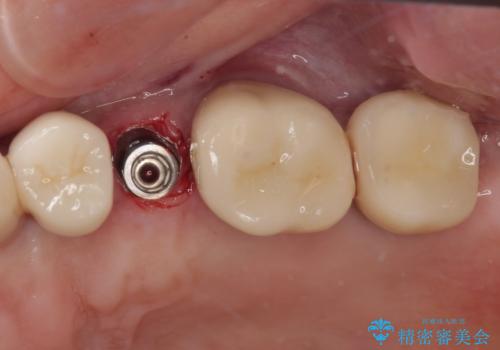

歯肉や歯槽骨の状態は良好であったため、抜歯即時埋入インプラントによる補綴治療を行うこととしました。

最小の来院回数で短期間で治療を終えることができました。